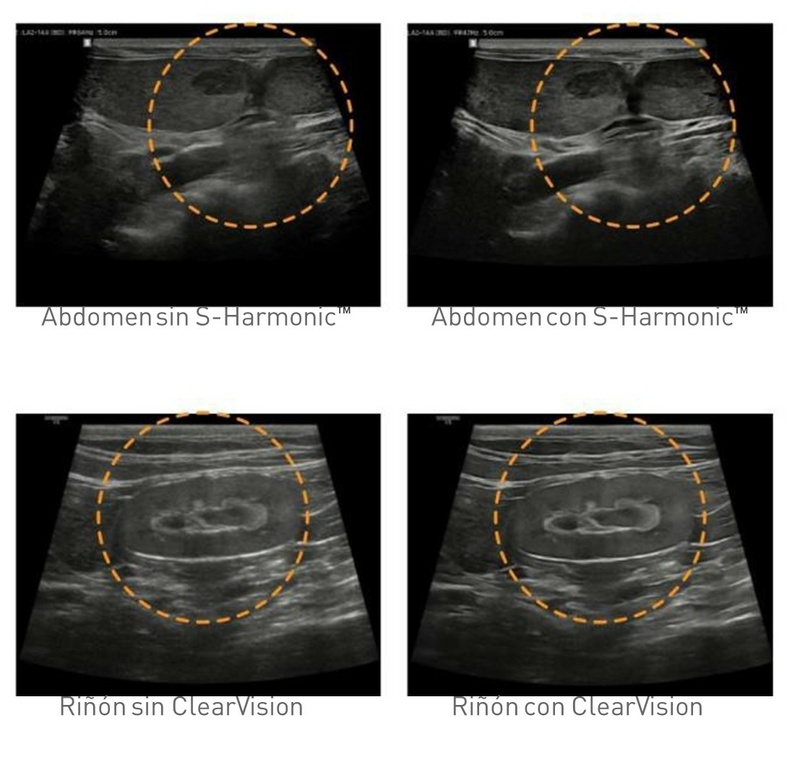

• ClearVision: Filtro de reducción de ruido para mejorar la calidad de la imagen 2D

• S-Harmonic: Prestación uniforme en toda el área de imagen de principio a fin